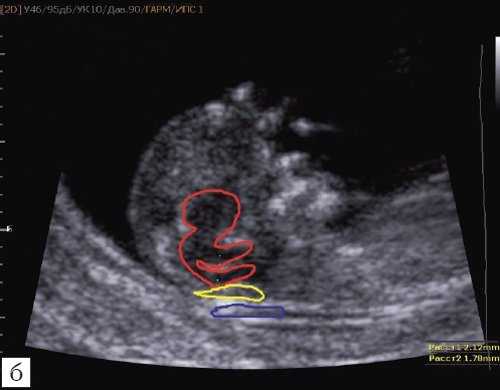

Так как речь идет о сроках первого скрининга, т.е. раннего осмотра, новый ультразвуковой маркер мы назвали "осьминожкой" (рис. 3).

а) Стрелками указана голова "осьминожки" - диэнцефалон (таламус).

б) Красный цвет - диэнцефалон (таламус), со стволом мозга (верхняя ножка) и IV желудочком (нижняя ножка); желтый цвет - большая цистерна головного мозга; синий цвет - воротниковое пространство.

Как сказано выше, имеет значение и измерение ножек "осьминожки", так среднее значение диаметра нижней ножки, т.е. IV желудочка в зависимости от КТР в срок 11-14 недель варьирует от 1,5 до 2,5 мм (рис. 4).

Рис. 4. Измерение и взаимоотношение ножек "осьминожки" - ствола мозга и IV желудочка у плода, беременность 12 недель.

Измерение ножек "осьминожки".

Красный цвет - диэнцефалон (таламус), со стволом мозга (верхняя ножка) и IV желудочком (нижняя ножка); желтый цвет - большая цистерна головного мозга; синий цвет - воротниковое пространство.